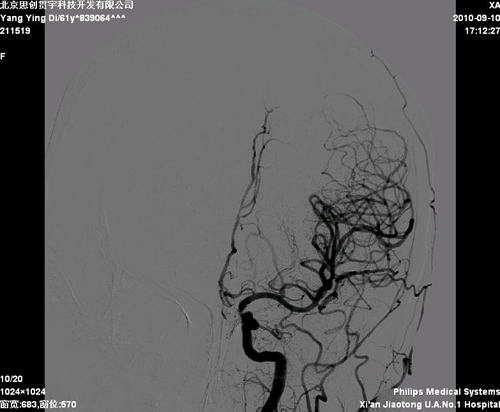

脑血管造影:右颈内动脉起始部30%狭窄;左颈内动脉起始部70%狭窄,基底动脉50%狭窄。

该患者诊断明确,有症状性颈动脉狭窄,且狭窄>50%,有进一步处理指征。患者左侧颈内动脉存在‘kinks征’,开口处迂曲,脑保护装置及支架输送系统可能难以通过病变,且患者颈动脉分叉不高,选择CEA更为合适。但此患者颈内动脉远端虹吸段也存在狭窄,患者此次的症状可能与二者同时相关,也可能只与其中一处相关,因此,处理颈内动脉起始部病变对预防远期同侧脑卒中有限。

2010年12月6日,由协作组张勤奕教授和王冬青教授在西安交大第一医院成功为该患者实施了左侧颈内动脉内膜剥脱术。